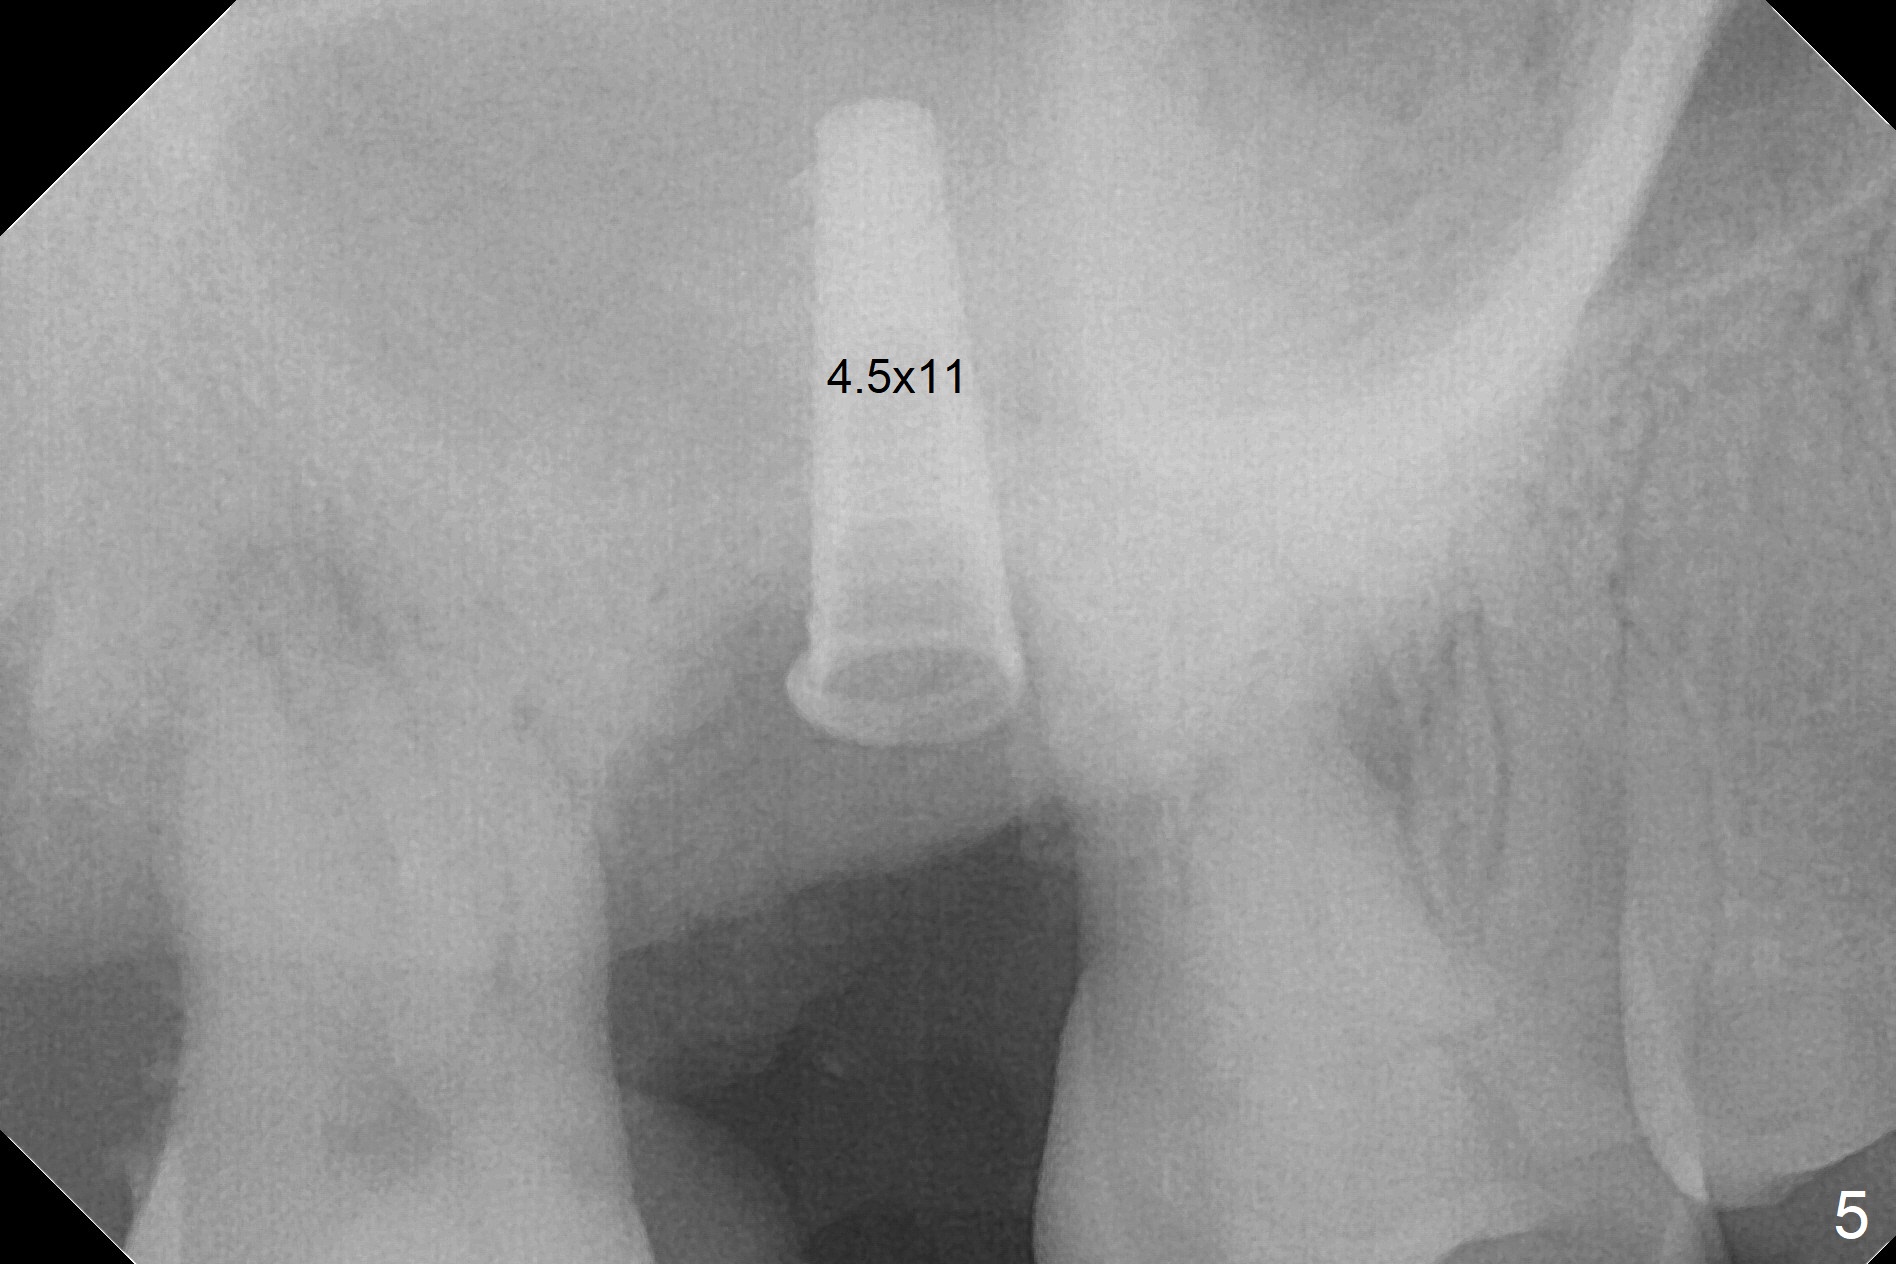

When the 59-year-old man returns for #24 implant placement, the tooth #2 is found to have crack (Fig.1,2 arrowheads), associated with buccal and palatal fistulae (*) and loss of amalgam (Fig.4 *). Abundant granulation tissue is attached to the roots of the affected tooth (Fig.3), indicating severe bone loss. There is a plateau associated with the septum and buccal sockets, which is the site of osteotomy. Magic split and 3 and 3.8 mm Magic Expanders are used to initiate osteotomy. After use of 4.3 mm Magic Drill for about 3 mm, Osteogen plug and allograft are used for sinus lift, followed by insertion of a 4.5x11 mm dummy implant (Fig.5). When a 5.5x9 mm dummy implant is placed with stability, it appears to be seated cervical (Fig.6,7). When a 6x9 mm IBS implant (definitive) is placed with a 6.5x5.5(4) mm abutment, they are seated too deep for provisional (Fig.8). The implant/abutment are removed and replaced by a 6.5x11 mm one in a shallower position; after trimming the same abutment as mentioned above (Fig.9), an immediate provisional is fabricated to keep bone graft in place. Fabrication of Tap with soft tissue markers will reduce the chance of miscalculation and waste of implants. The coronal threads of the implant are covered with bone 6 months postop (Fig.10). One month later when a permanent crown tries in, the implant is found to be loose and tender. A healing abutment is placed. Six months later, the patient returns for crown retry-in. The tooth #1 seems to have shifted mesially (Fig.11 arrow). When the abutment is placed, the implant remains tender and loose. After implant removal with a wrench, there is no granulation tissue or bony defect, including the intact sinus floor (Fig.12 <). Since the tooth #1 has deep periodontal pockets and mobility, the tooth is extracted with abundant granulation tissue. After debridement, Osteogen plug is placed in the socket of #1, while Vanilla graft is placed at the site of #2 (Fig.13 *). Three weeks later, the socket of #2 heals with exposure of Osteogen plug (Fig.14 (B: buccal)).